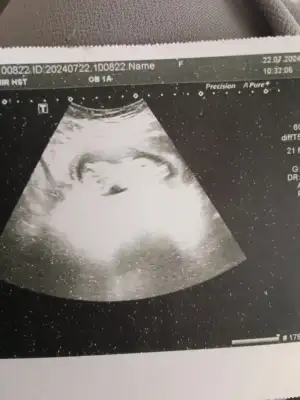

Ya evet ikizde karın daha çabuk büyüyor. Benimde çıktı ama o kadar değilAmiinnn inşallahgruba çok bakamadım. Herkesin nasıl gidiyor? Benim mide bulantılarım hiç geçmedi. Hatta biraz arttı. İlaç kullanmama rağmen hala şiddetli. Sürekli kilo veriyorum. Ama ikiz olduğu için sanırım karnım kocaman oldu. 6 aylık gibi neredeyse. Kardeşim 2 hafta görmedi sonra şok oldu inanamadı. Sizlerde durum ne?

Bizim bacak arasına baktı dedi ki pipi göremiyorum ama birkaç haftaya netleşirBizim ikili testte de ense kalınlığı 1 mm çıktı çok şükür. 12+6 dedi. Normalde 12+2 diye biliyordum. Cinsiyet erken dedi bana da